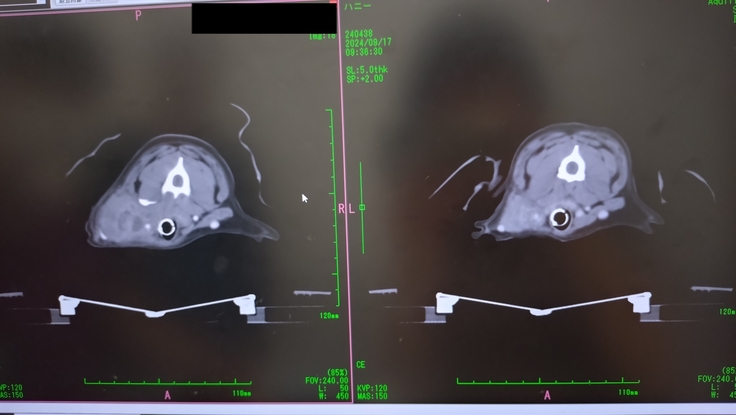

9月17日放射線4回目

9月17日4回目の放射線治療

この日はまたCTを撮り、扁桃腺とリンパ節に4回目の放射線の照射をした。

CTで、扁桃腺とリンパ節に転移した腫瘍はかなり小さくなったのが分かったけど、右前足の付け根の骨に転移が見つかってしまいました😭

この日は既に、扁桃腺とリンパ節への放射線照射は終わっていたので、午後の予約の合間で骨転移の部分の放射線照射もやっていただけることになった。全身麻酔を1日で2回もすることになりそれも心配だった。